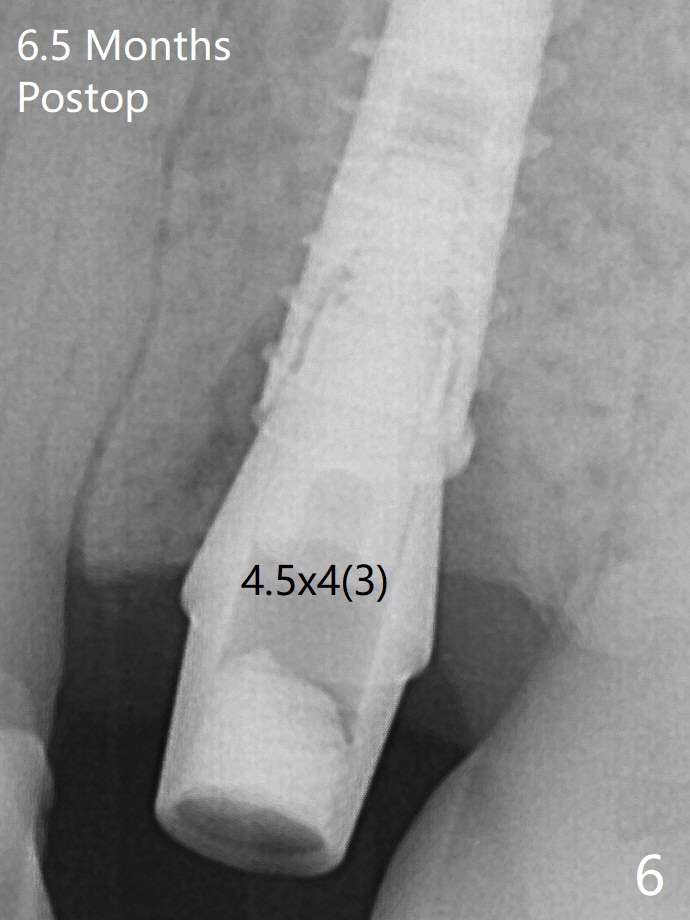

A 4x13 mm IBS implant is seated incompletely. The osteotomy is further enlarged by 3.8 mm Magic Drill for 11 mm and deepened with 3 mm drill until 18 mm. Finally the implant is placed at a satisfactory level with insertion torque > 50 Ncm (Fig.5). The patient chooses to return for impression 6 months postop (Fig.6). The abutment changes to a 4x4(4) mm one. The crown is recemented nearly 2 years post cementation, which is related to distal and deep placement of the implant and bruxism (Fig.7).